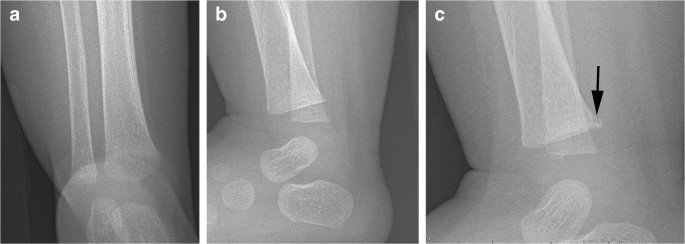

radiological dating of fractures and even less relating fractureagetochildabuse . Themostcomprehensivereview is byO'ConnorandCohen .' . . . Fresh fractures , including metaphyseal fractures , have sharply defined margins . With the development of an osteoclastic response to necrotic bone the fracture ends

These metaphyseal abnormalities were identified from postmortem radiogra-phy and correlated with microscopy . The au-thors concluded the metaphyseal alterations represented partial or complete planar micro- fractures that transected the primary spongio-sa adjacent to the growth plate . These micro- fractures usually resembled a "bucket-handle"

Specific fractures . A number of fractures have been recognised as highly specific to non-accidental injuries (rather than accidental injury) . They include: metaphyseal fracture (so-called bucket handle fracture or corner fracture ) present in up to 39-50% of abused infants <18 months; said to be virtually pathognomonic of NAI; rib fractures